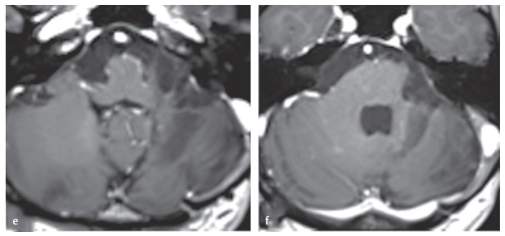

術(shù)后4年,患者可以完全獨(dú)自生活,髓質(zhì)(圖e)和腦橋(圖f)軸位t1加權(quán)磁共振增強(qiáng)掃描未見腫瘤殘留或復(fù)發(fā)。